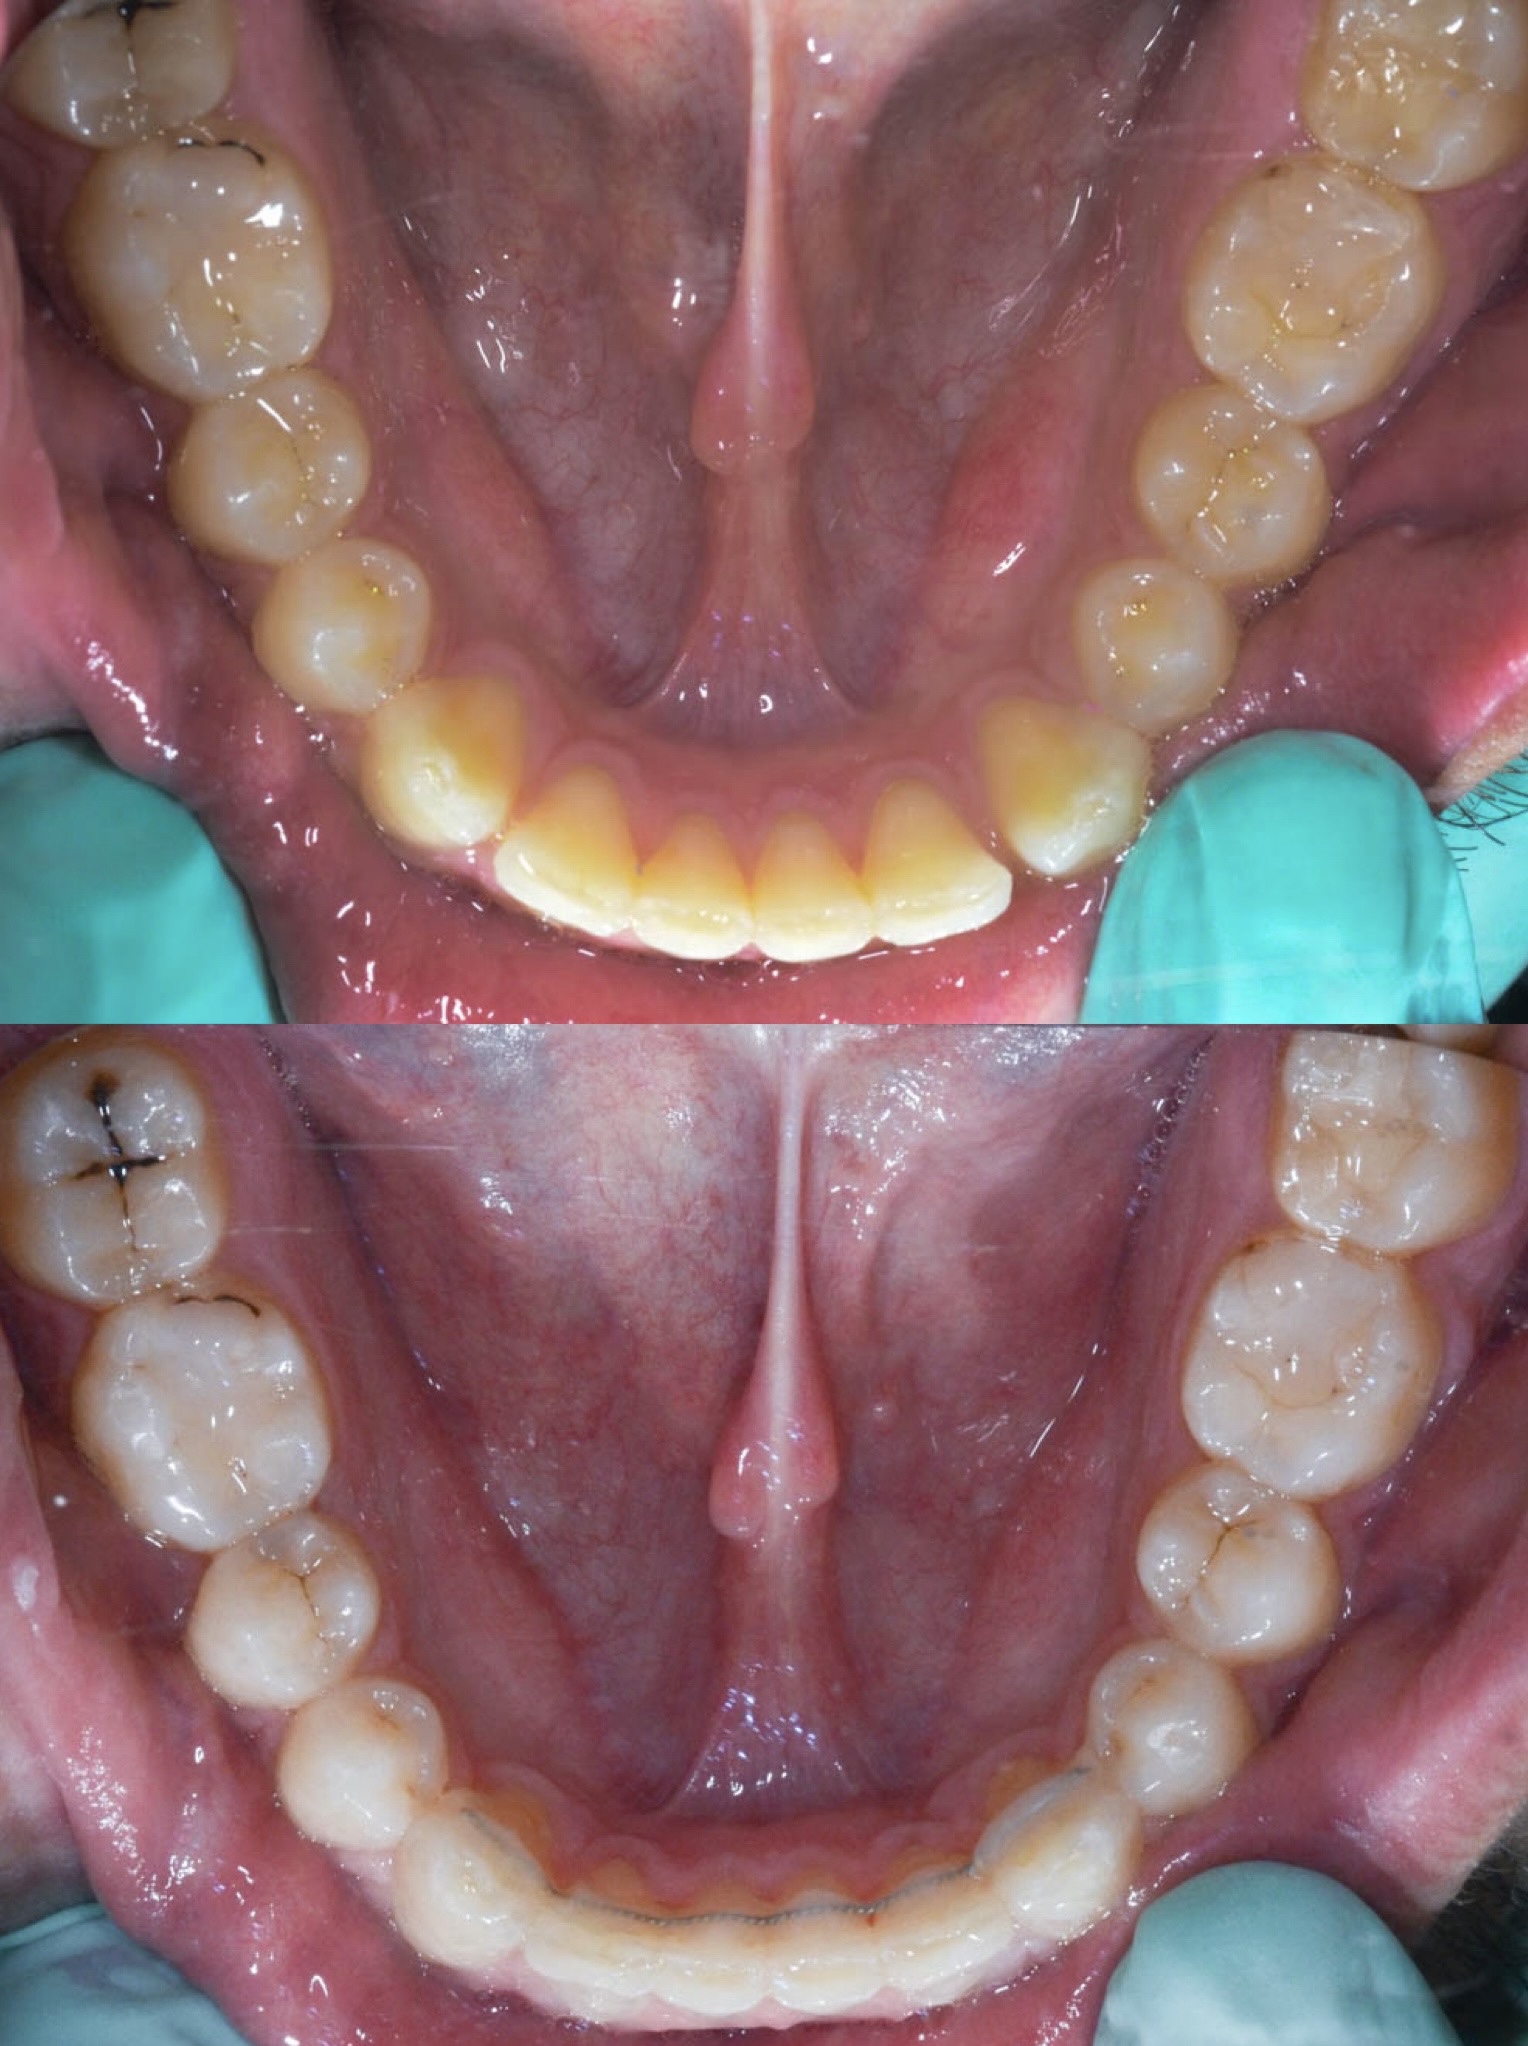

U galeriji slika su prikazani klinički slučajevi ovakvih odraslih pacijenta bilo da se radi samo o ortodontskoj terapiji ili predprotetskoj ortodonciji.

Kompresija –fiksni aparat i ekstrakcija jednog donjeg sjekutića

U sljedećem primjeru prikazan je pacijent s kompresijom koji je već bio u ortodontskoj terapiji. Za rješavanje kompresije donje čeljusti izvađen je sjekutić. Nkon terapije je došlo i do smanjenja recesija na očnjacima jer smo pomakli zubni korijen u bolji položaj.